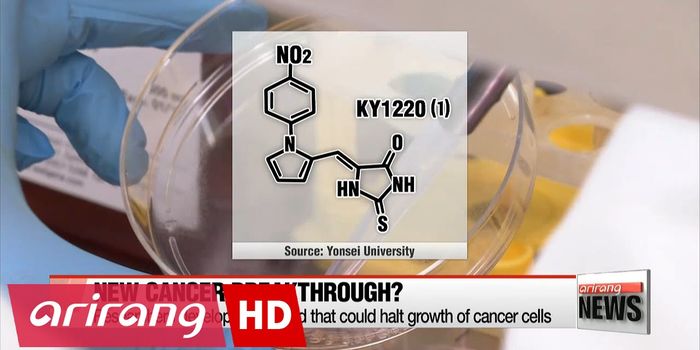

NOV 10, 2017VideosMedicine has been attempting to fight cancer for decades, but now scientists are calling for something better. For examp ...